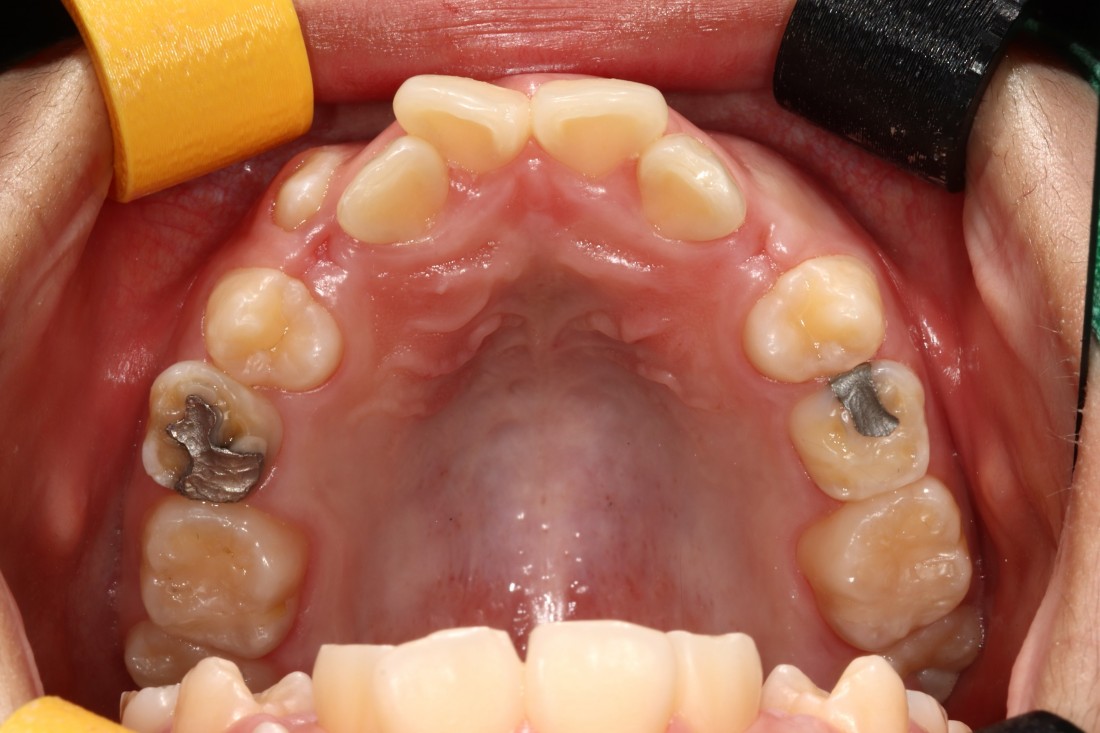

광주 덧니교정 치과에서는

덧니교정 시에

발치를 하는 경우도 있고,

비발치로 진행하는 경우도 있습니다.

치료계획은 모두 경험이 풍부한

교정전문의 대표원장님과

교정 전 정밀검사 결과를 토대로

오랜시간 세심한 상담 후에

결정하고 있습니다.

교정전문의가 봤을 때

발치가 꼭 필요한 경우가 있기 때문에

다양한 덧니교정 케이스와 비교하며

나만을 위한 치료계획을 세우고 있습니다.

![]() | ![]() |

광주 덧니교정 치과는

대표원장인 제가 직접

다양한 교정 전/후 케이스를

공유하고 있습니다.

다양한 각도에서 촬영한

교정 전/후 사진을 직접 확인할 수 있어

광주 덧니교정 치과의

실력있는 진료를 증명하고 있습니다.

발치를 진행한 덧니교정이나

비발치 덧니교정 모두

다양한 케이스를 보유하고 있기 때문에

나의 구강구조와 비교해보면서

성공적인 교정치료 결과를

기대해보실 수 있습니다.